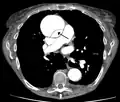

Computed tomography

Computed tomography angiography is a fast, non-invasive test that gives an accurate three-dimensional view of the aorta. These images are produced by taking rapid, thin-cut slices of the chest and abdomen, and combining them in the computer to create cross-sectional slices. To delineate the aorta to the accuracy necessary to make the proper diagnosis, an iodinated contrast material is injected into a peripheral vein. Contrast is injected and the scan performed using a bolus tracking method. This type of scan is timed to injection to capture the contrast as it enters the aorta. The scan then follows the contrast as it flows through the vessel. It has a sensitivity of 96 to 100% and a specificity of 96 to 100%. Disadvantages include the need for iodinated contrast material and the inability to diagnose the site of the intimal tear.

-

CT with contrast demonstrating aneurysmal dilation and a dissection of the ascending aorta (type A Stanford) -